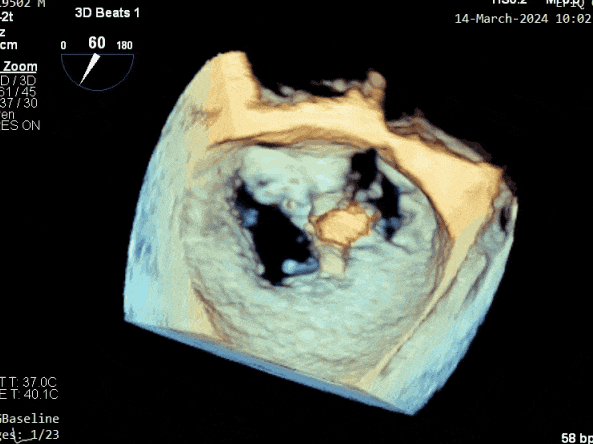

二尖瓣后叶活动受限,呈房源性栓系,以P3区为重,二尖瓣前叶假性脱垂,二尖瓣瓣环前后径49mm,左右径40mm。

PISA法测r=12mm,EROA=0.72cm2,RVOL=100ml,RF 26%。LVEDD 57mm,左房71*59*77mm,右房55*69mm,LVEF 70%。

超声提示:

二尖瓣反流(重度,4+级,Carpentier I型)

三尖瓣反流(轻度)

主动脉瓣反流(轻度)

双房及心耳内未见确切血栓回声